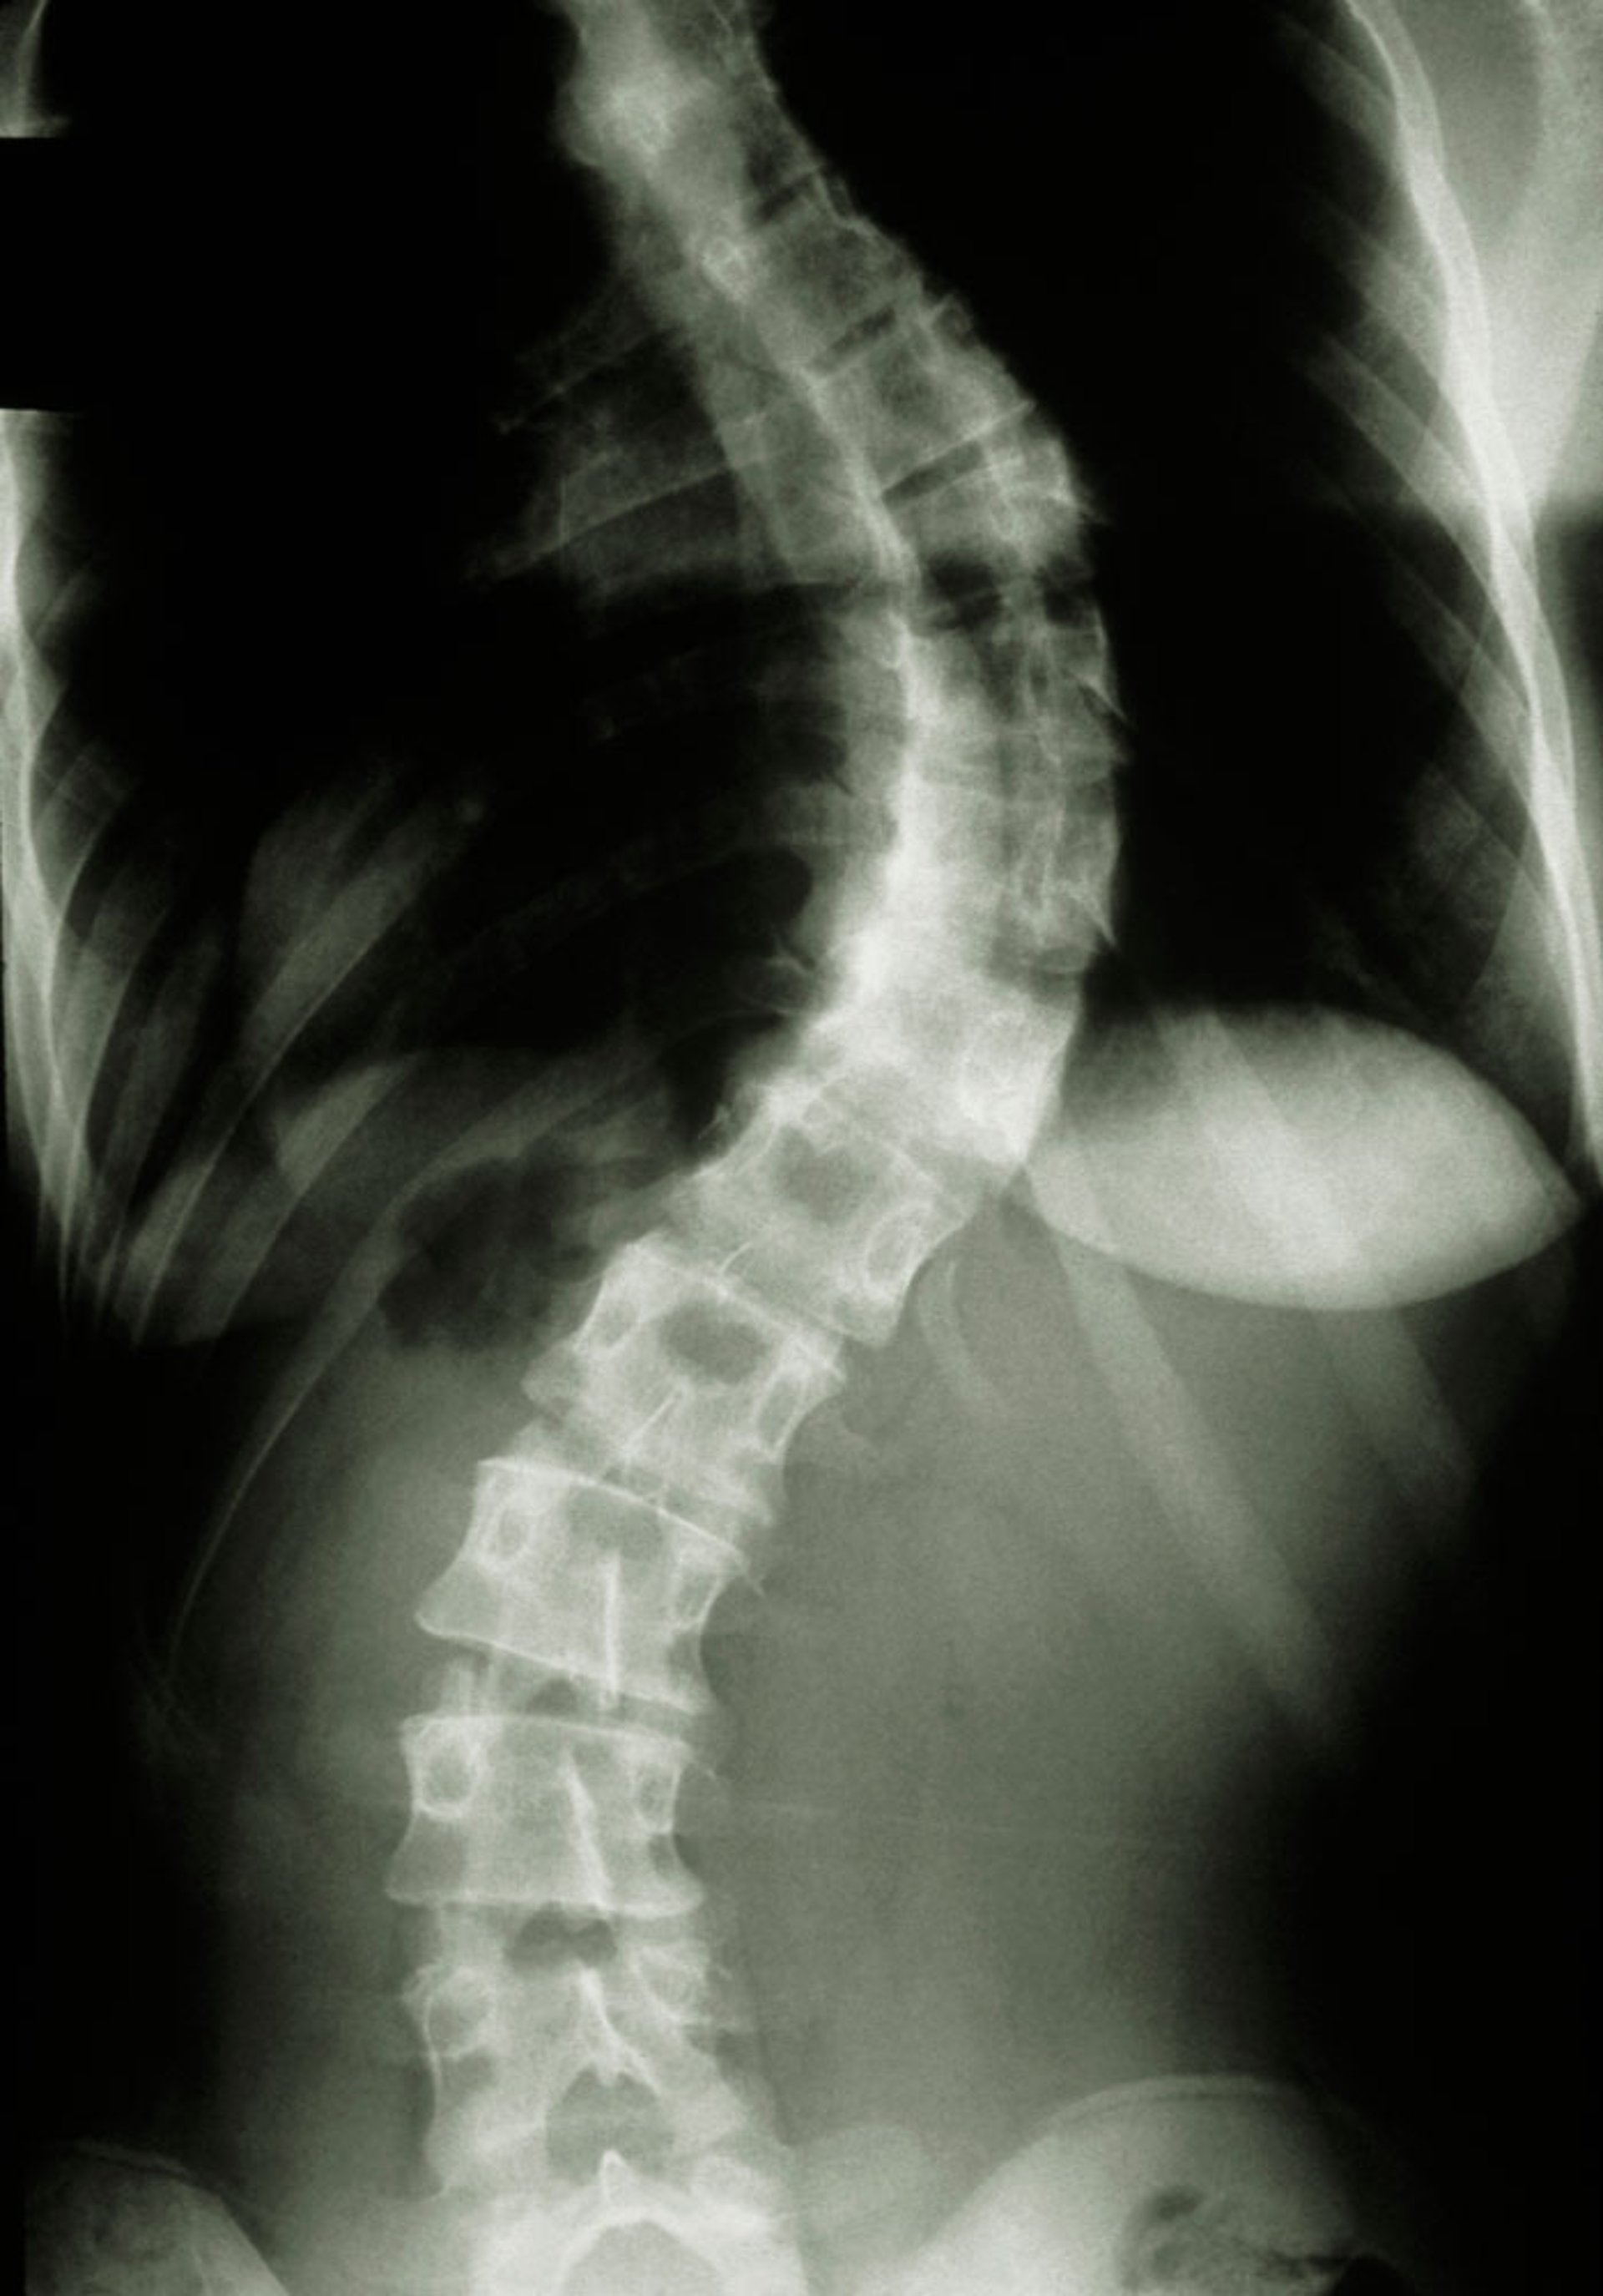

Spinal Radiograph (Scoliosis)

This radiograph shows scoliosis.

A Cobb angle of 20° is required to count towards the systemic score when evaluating for Marfan syndrome.